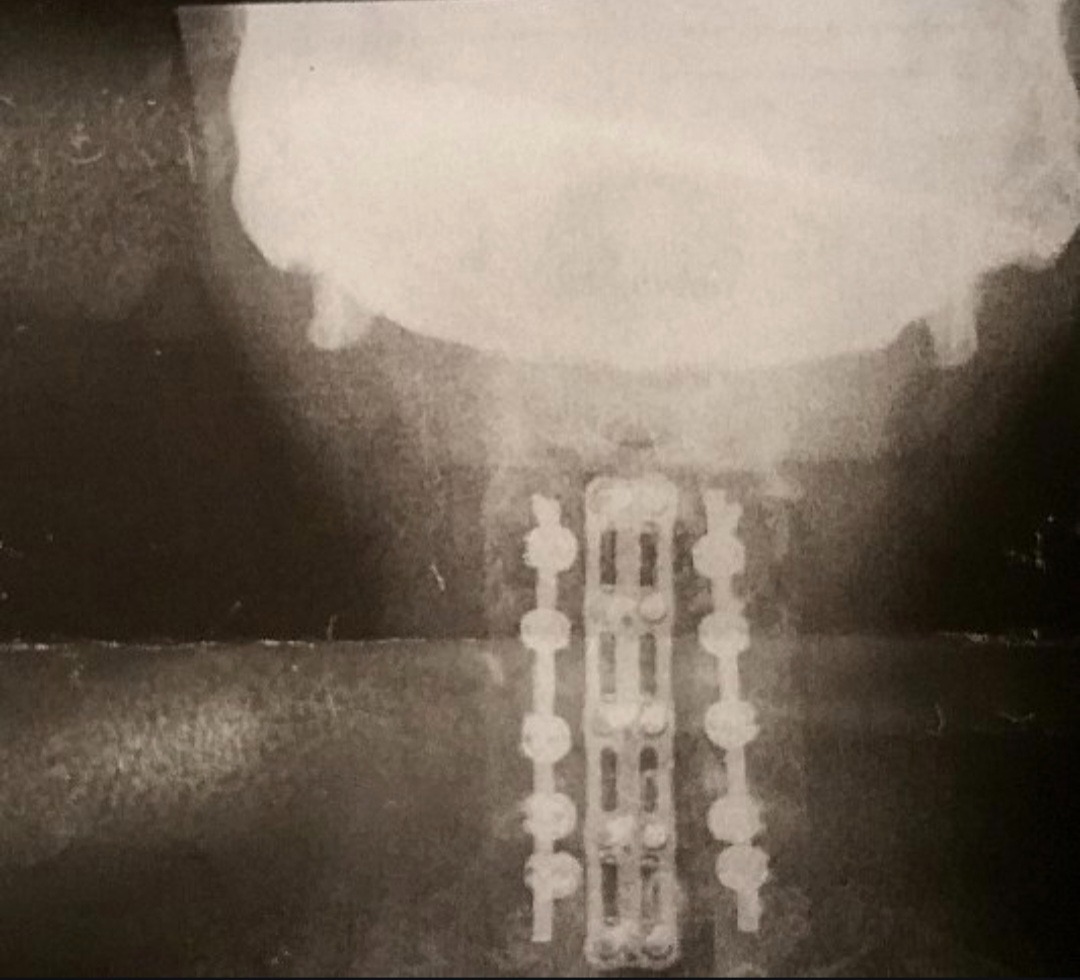

My name is Edward, and I never imagined my life would take the turn it has. A few years ago, during what should have been a routine procedure, I was tragically dropped in the operating room. That accident broke my neck from C3 to C7, leaving me with devastating injuries that required 20 screws, 2 rods, and a steel plate to hold my spine together.